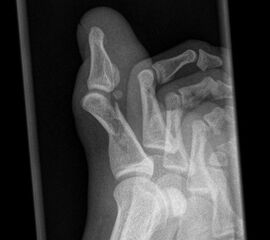

Zehe dorsoplantar (dp)

Positionierung:

• Der Patient sitzt auf dem Untersuchungstisch.

• Der Fuß steht plan auf der Kassette.

• Der Zentralstrahl wird auf die betreffende Zehe zentriert.

• Die Röhre ist 0° vertikal ausgerichtet.

Kennzeichen des Röntgenbildes:

• Überlagerungsfreie Darstellung der betroffenen Zehe incl. des distalen dazugehörigen Mittelfussknochens.

• Der Weichteilmantel ist erkennbar.

Besondere Bemerkungen zum Beispielbild:

• Großzehe dp bei Grundgliedfraktur mit diaphysäre Trümmerzone.

• Sesamoid im Ansatzbereich der Flexor hallucis longus Sehne.